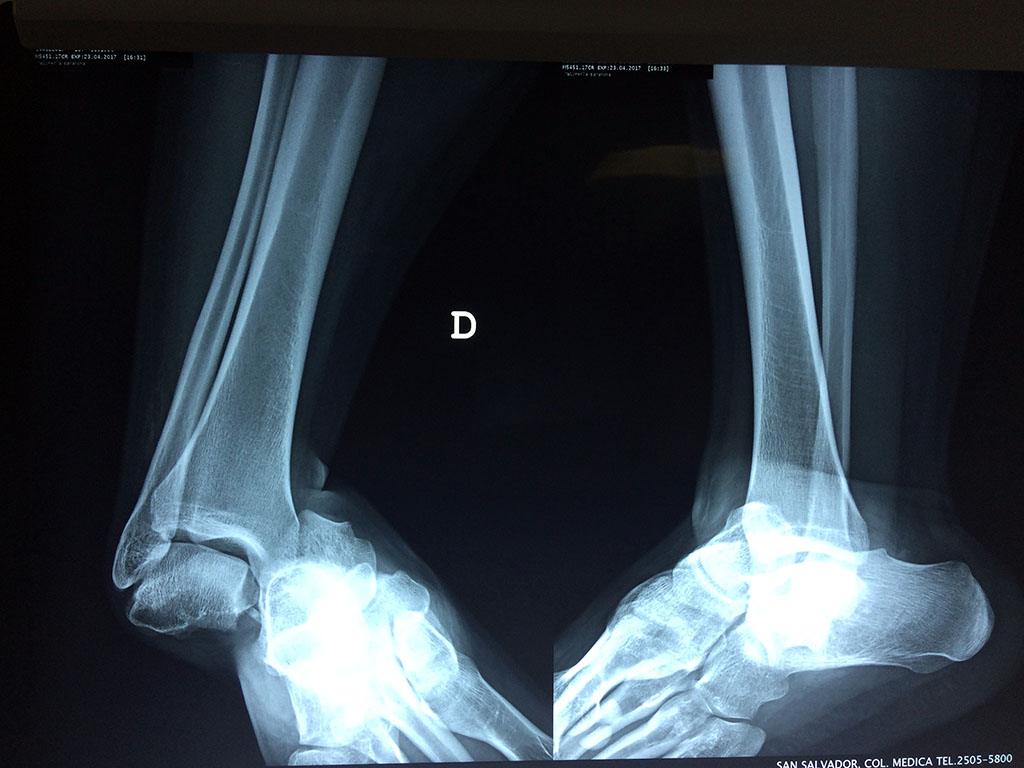

Cuando se necesita cirugía, es probable que esta implique el uso de clavijas de metal, tornillos o placas para sostener los huesos en su lugar mientras la fractura se consolida. Los elementos de soporte pueden ser temporales o permanentes.